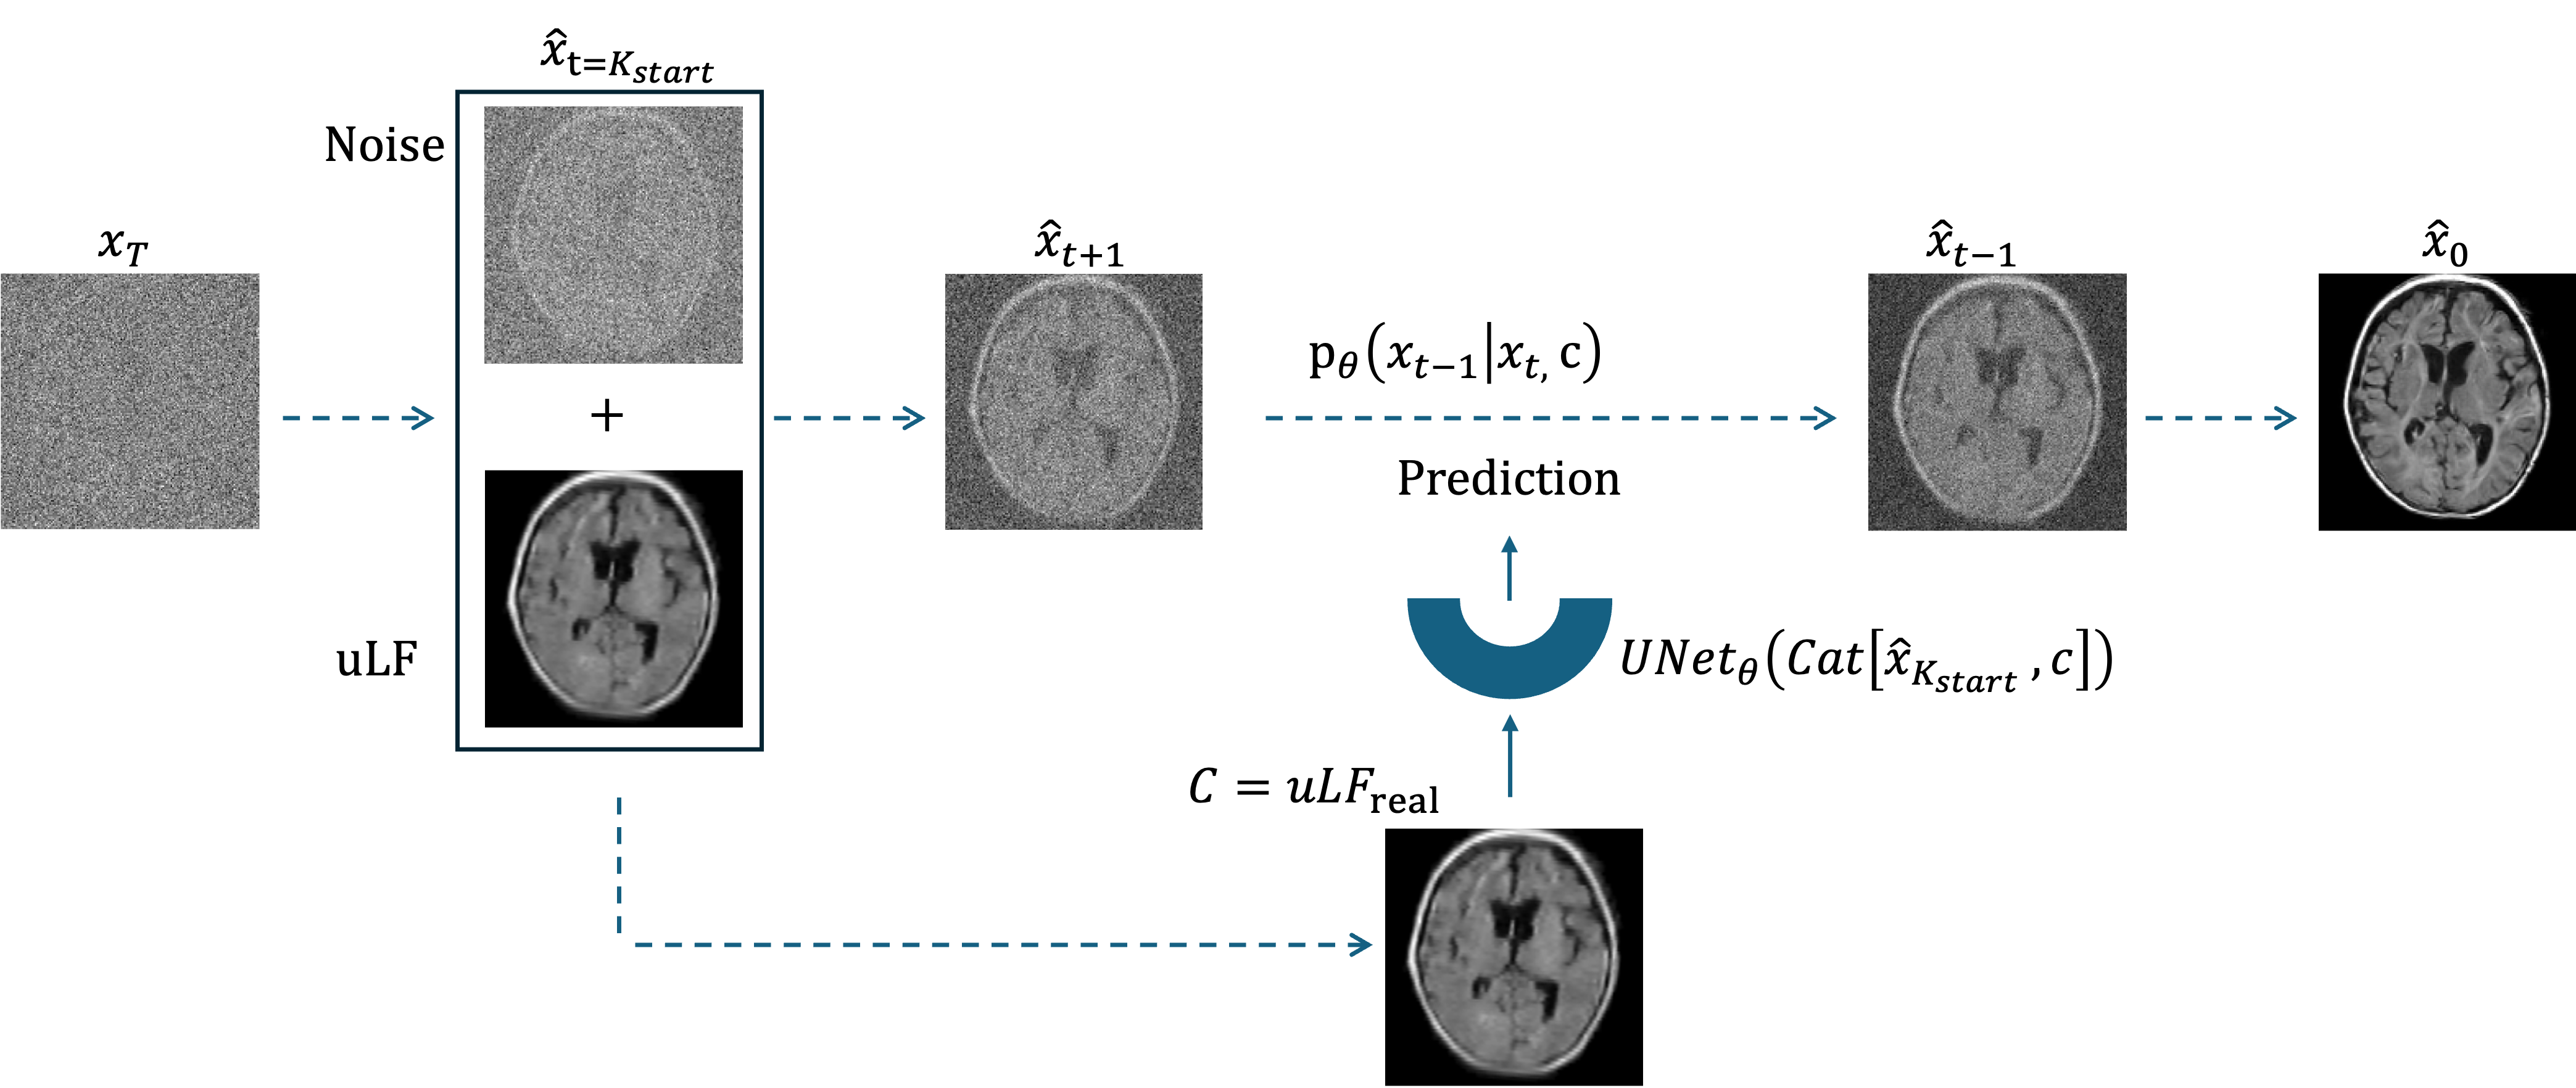

Refer to caption

((a)) Training pipeline.

((b)) Inference pipeline.

Fig. 2: Overview of the MRIQT framework showing the training (left) and inference (right) stages. Diffusion process from x0x_{0} to xTx_{T}, where x0x_{0} is HF reference and xtx_{t} is noise (\xleftarrow{}). At each timestep tTt\in T, the UNet, conditioned on c=uLFsimc=\text{uLF}_{\text{sim}} is trained to predict the added noise/v. Inference/sampling starts from x^t=Kstart=c+ϵ\hat{x}_{t=K_{start}}=c+\epsilon, where c=uLFrealc=\text{uLF}_{\text{real}}, progressively denoising the input until x0^\hat{x_{0}}.

MRIQT extends the DDPM [ho2020denoising] to 3D volumes. The forward process adds Gaussian noise xt=α¯tx0+1α¯tϵx_{t}=\sqrt{\bar{\alpha}_{t}}x_{0}+\sqrt{1-\bar{\alpha}_{t}}\epsilon (Figure 2(a)), while the reverse model learns to predict and remove the noise conditioned on the uLF input. Instead of unconditional sampling, we use image-to-image diffusion, initializing denoising from a partially noised uLF scan, which preserves structural fidelity while allowing generative refinement (Figure 2(b)), as in [saharia2022image].